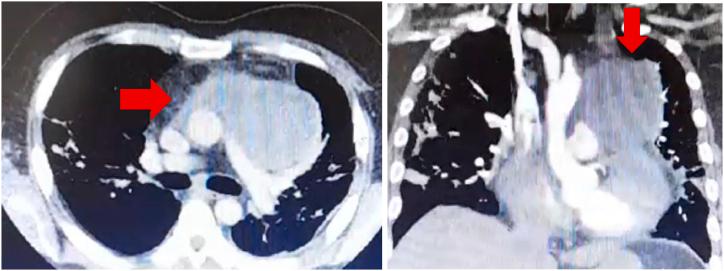

我们介绍了一名45岁宝石矿工的罕见病例,该患者因心包积液已接受心包开窗术。他因复发性心包积液和计算机断层扫描肺动脉造影扫描诊断出的前纵隔肿块前来就诊。心包液培养确诊红球菌为该病的病原体。据我们所知,这是红球菌感染极为罕见的表现,尚未见文献报道。